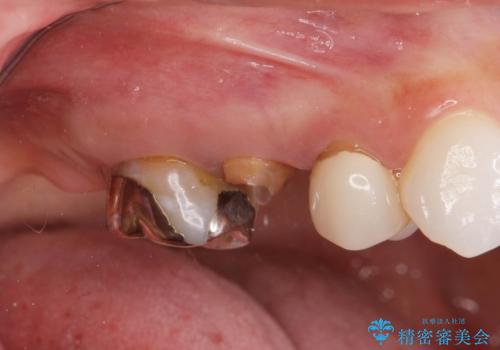

- 「奥歯のクラウンが取れてしまったので診てほしい。」とセラミック治療を希望され来院されました。

診査を行ったところ、クラウンの取れた歯は、割れてしまっており再度クラウン装着が難しい状況でした。

抜歯を行ったのち、ブリッジ製作を行うことで咬合機能の回復を計画します。